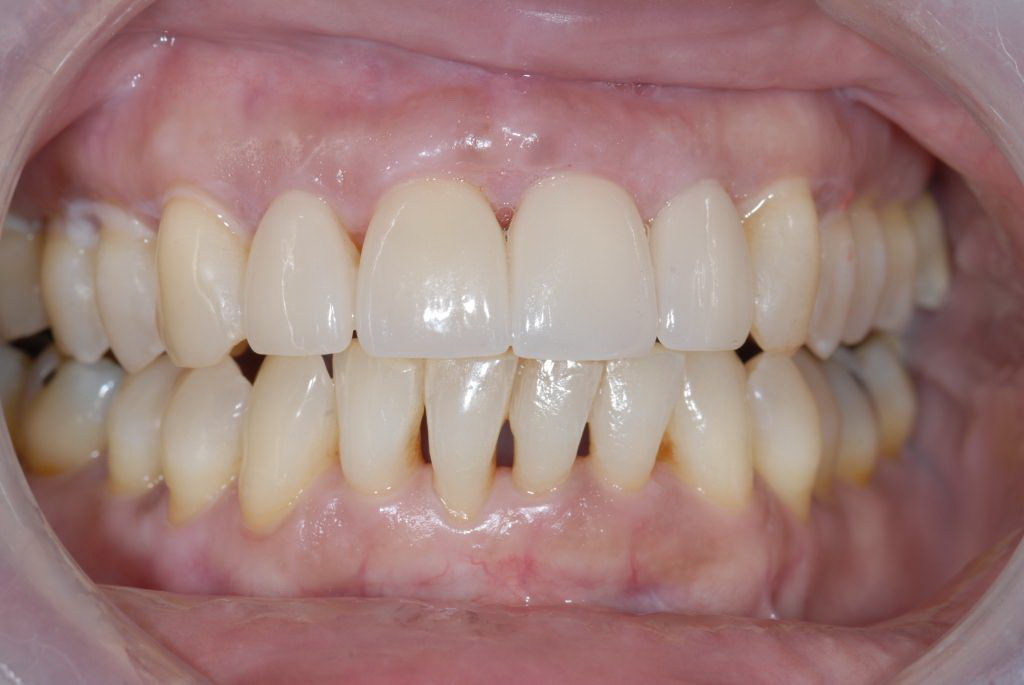

A patient in her 60s wanted to improve her smile but declined orthodontic treatment in favor of porcelain veneers (Figure 13). However, addressing her 8-mm pocket was the first step. The practitioner created biologically clean root surfaces using ultrasonic open-flap debridement, finishing burs, and manual tool instrumentation. Next, a mineralized freeze-dried bone allograft saturated in platelet-derived growth factor (Figure 14) using chemotaxis pulled the stem cells capable of regeneration into the site where repopulation was needed. Prior to closure, a resorbable membrane, polylactic acid-guided tissue regeneration—known for periodontal regeneration—was used (Figure 15). At 10 weeks, adequate healing had occurred. The patient at 6 and 10 weeks showed continued healing. Although some postoperative recession was evident, probing depths were less than 2 mm, and the patient was referred back to the restorative dentist for restorative therapy. As of this writing, she has not lost any teeth and is periodontally stable (Figure 16).

The final restorative situation. (Restorative therapy by Dr. B. Wilk, Chalfont, PA.)

Figure 16